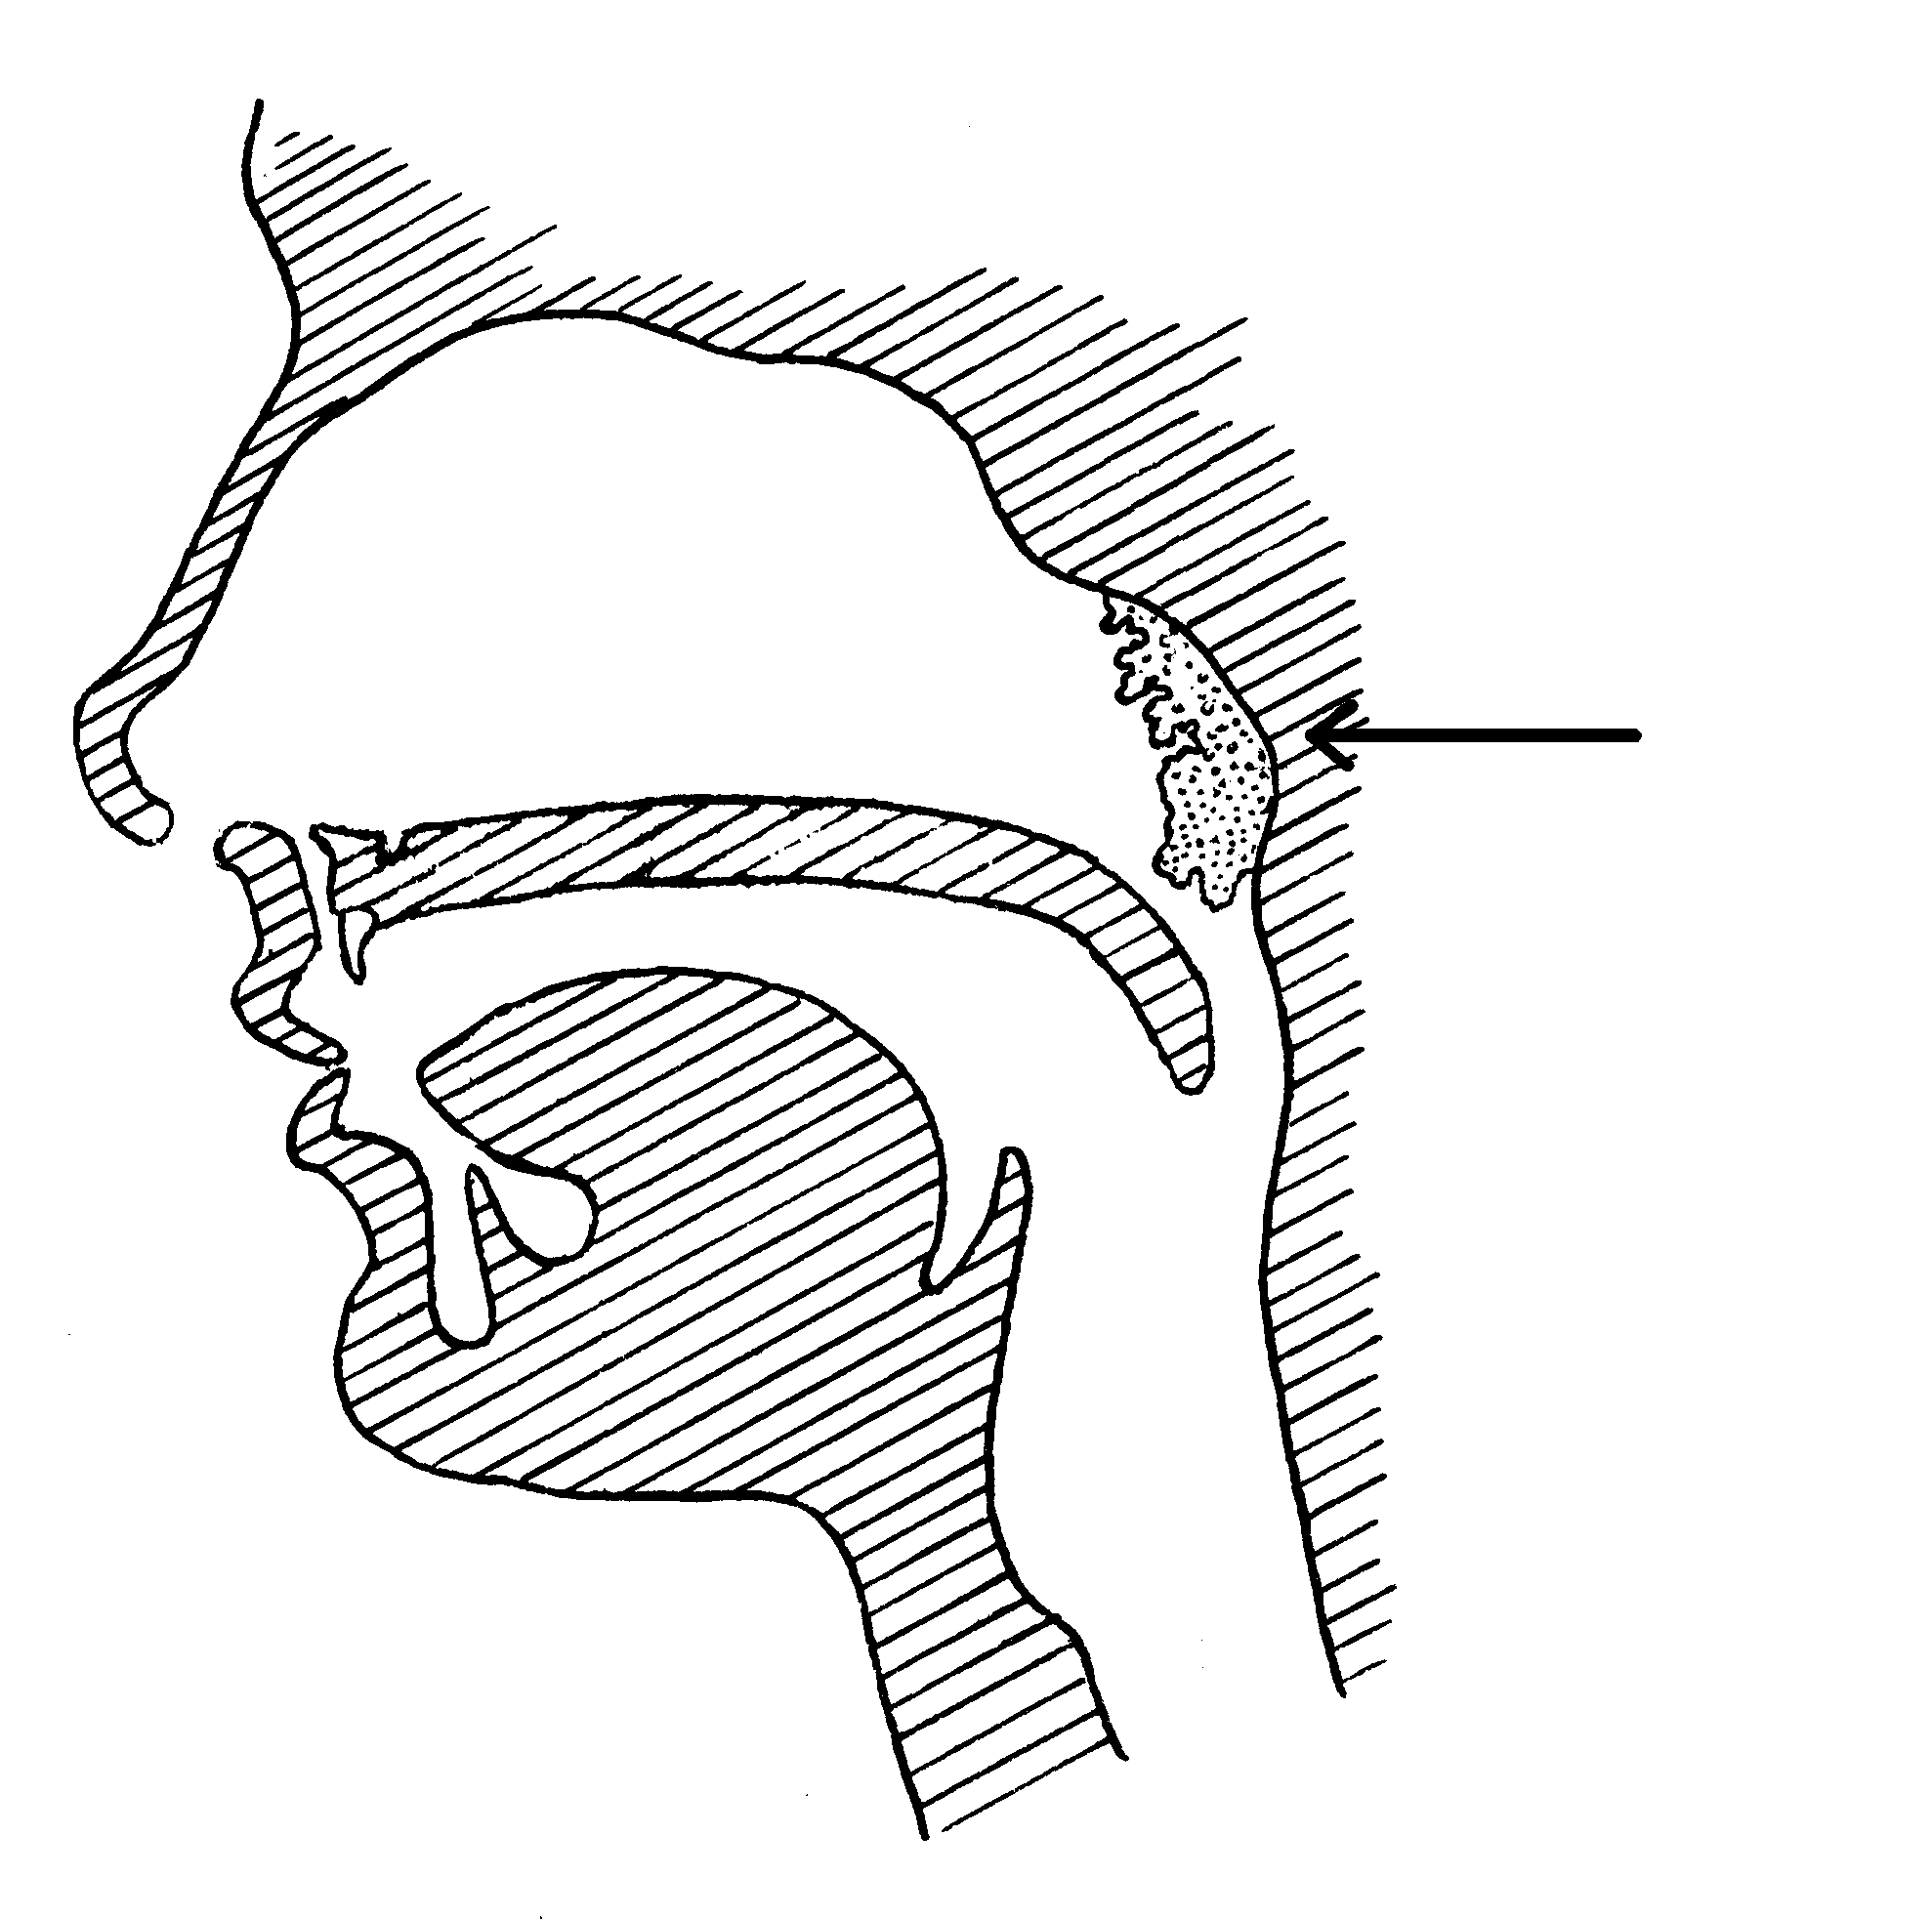

Migdałek zwany gardłowym usytuowany jest w części nosowej gardła, nie jest on widoczny w badaniu przez usta. Usytuowany został z tyłu nosa i widoczny jest przez nos lub w badaniu przy użyciu lusterka.

Nowoczesną techniką oceny przerostu migdałka jest metoda endoskopowa przy użyciu fiberoskopu, czyli giętkiego, cienkiego przewodu zawierającego światłowód i zakończonego kamerą, który wprowadza się przez nos lub przez jamę ustną, a obraz w powiększeniu widoczny jest na ekranie monitora. Stosuje się także bezpośrednią metodę palpacyjną lub zdjęcie rentgenowskie.

Usunięcie migdałka czyli adenotomia jest zabiegiem chirurgicznym polegającym na usunięciu lub ścięciu nadmiaru tkanki limfatycznej migdałka gardłowego, zwanego inaczej trzecim migdałkiem. Zabieg ten musi być poprzedzony badaniem wykonanym przez lekarza laryngologa. Specjalista stawia diagnozę na podstawie charakterystycznych objawów towarzyszących przerostowi migdałka, a także po wykonaniu rynoskopii tylnej (wymagającej użycia lusterka laryngologicznego) i przedniej. Niekiedy lekarz decyduje się na badanie endoskopowe z użyciem miękkiego, giętkiego fiberoskopu wprowadzanego do nosogardzieli. Po postawieniu diagnozy wybierane jest najodpowiedniejsze leczenie. Wskazaniami do adenotomii są : znaczne ograniczenie drożności nosogardzieli, poważne trudności w oddychaniu przez nos, występowanie bezdechów sennych, chrapania, twarz adenoidalna, wady zgryzu, nawracające/przewlekłe zapalenie nosa i zatok przynosowych, przewlekłe/nawracające wysiękowe zapalenie ucha. Zabieg wykonuje się najczęściej po trzecim roku życia, ze względu na częstą samoistną inwolucję (zanik) tkanki limfatycznej u dzieci starszych. Najbardziej preferowaną formą znieczulenia stosowaną w adenotomii jest znieczulenie ogólne. Pacjent zasypia na czas zabiegu, nie czuje w ogóle bólu i nie pamięta tego co działo się podczas operacji. Jest to szczególnie korzystne dla dzieci. Ogranicza się im w ten sposób stres związany z salą operacyjną i kontaktem z personelem medycznym. Czas wykonania adenotomii jest krótki i waha się między 20-30 min. Lekarz adenotomem (narzędziem zgiętym na końcu w kształcie litery „U”) usuwa jednym, zdecydowanym ruchem trzeci migdałek. Po wycięciu struktury, występujące krwawienie jest na ogół nieznaczne i ustępuje samoistnie. Rany nie trzeba zaopatrywać szwami. Goi się ona dość szybko. W pierwszych dniach po operacji należy stosować odpowiednią dietę ograniczającą bardzo gorące, kwaśne i ostre potrawy. Pacjent podczas zabiegu oraz zaraz po wybudzeniu otoczony jest profesjonalną opieką personelu medycznego. Zostaje zaopatrzony w leki przeciwbólowe. Kiedy stan chorego jest dobry, możliwe jest wypisanie go do domu jeszcze tego samego dnia. Najczęściej jednak wymagana jest krótkotrwała hospitalizacja. Powikłania zabiegu występują bardzo rzadko. Należą do nich zakażenie rany pooperacyjnej, długotrwałe krwawienie, uszkodzenie struktur leżących w pobliżu migdałka (bardzo rzadko), powikłania związane ze znieczuleniem.